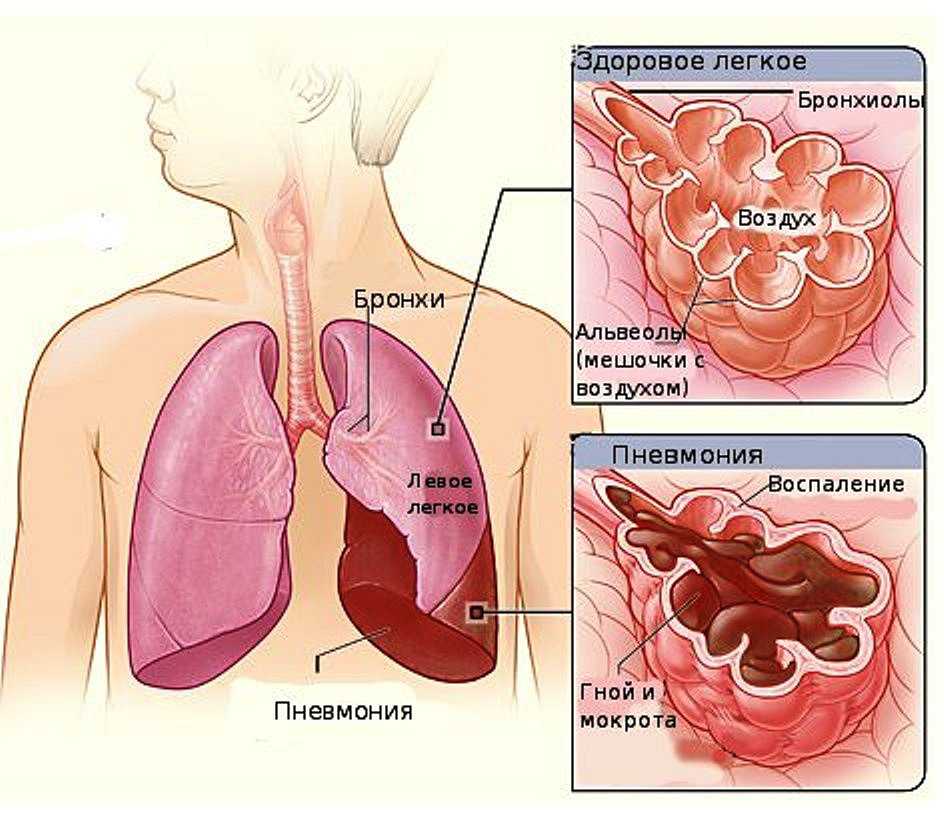

Коронавирус переходит в нижние дыхательные пути, поражает альвеолы легких. Начинается воспаление. Это нарушает газообмен, приводит к одышке. Даже после восстановления от пневмонии у человека может длительное время оставаться дыхательная недостаточность.

Пневмония при коронавирусе – распространенное явление. Причем многие болезненные симптомы могут быть незаметными. Проблема усложнена большим количеством очагов воспаления в легочной ткани с блокировкой альвеол легких. В данном случае необходима своевременная медицинская помощь.

- альвеолит;